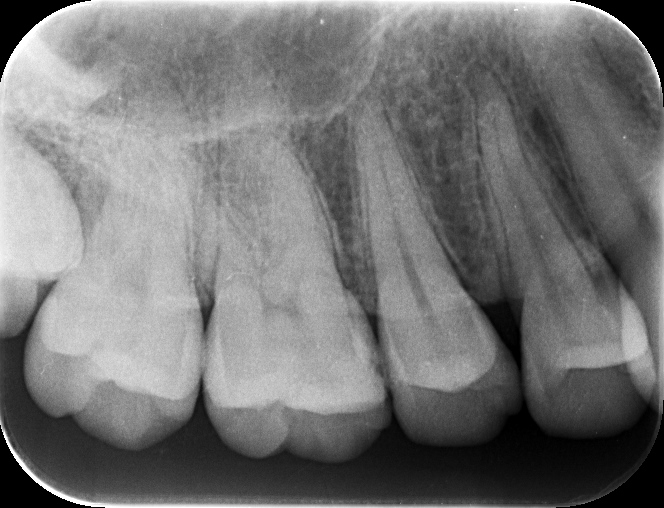

レントゲン上と、実際の見え方

上の写真が処置した部位なります。写真からは、間に黒い部分があるのが見えると思いますが、レントゲン上ではどうでしょうか?

問題の部位は、ここになります。はっきりしたものは映っていません。では、その部分の実際はどうだったのかというと・・・